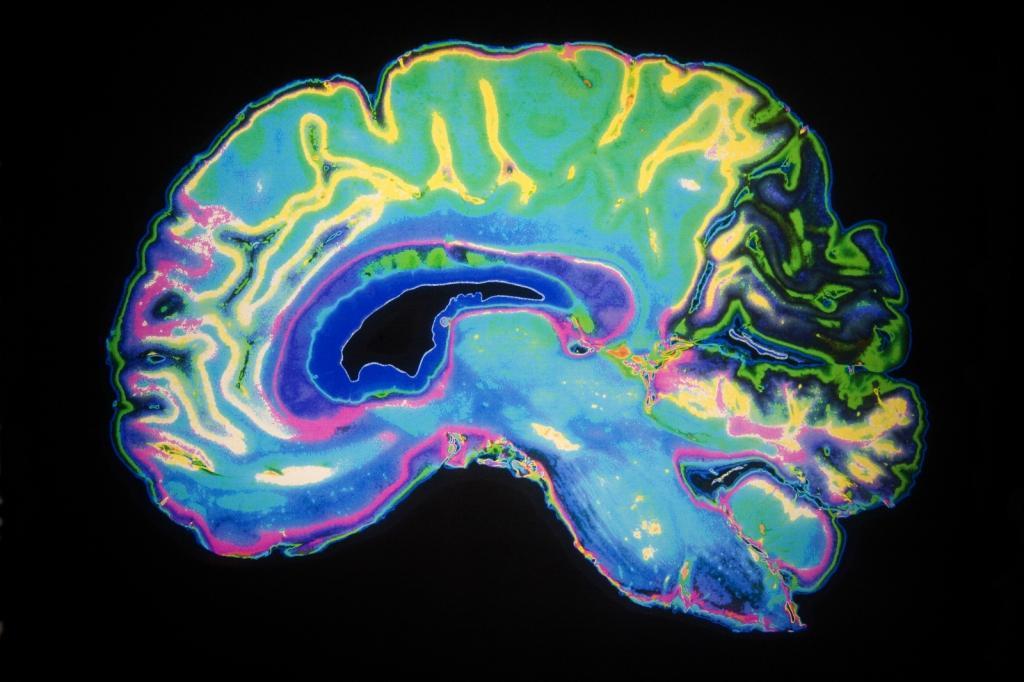

多亏了杜克大学体内显微镜研究中心领导的一组研究人员的努力,现在大脑成像的清晰度达到了6400万倍。利用核磁共振成像技术,他们能够以有史以来最高的分辨率捕捉到整个老鼠的大脑。

从这个角度来看,新图像的分辨率就像从一个像素化的8位图形到查克·克洛斯(Chuck Close)绘画的超现实主义细节。新图像中的单个体素只有5微米,比临床MRI体素小6400万倍。